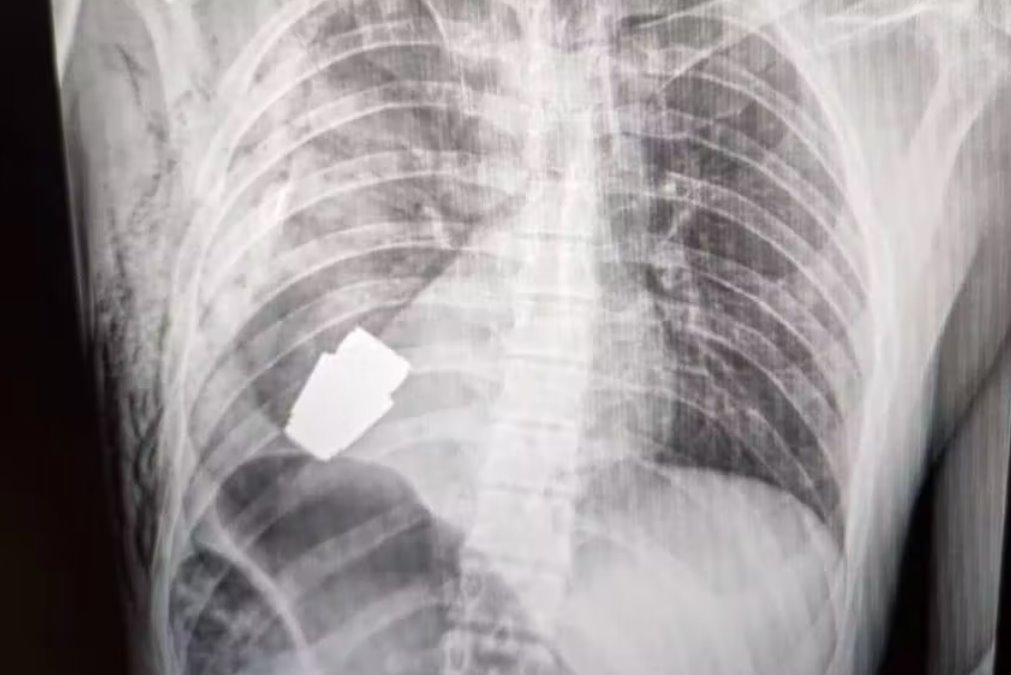

軍方發(fā)布了一張位于一個(gè)人軀干內(nèi)的手榴彈的X光片和一張Verba在手術(shù)后手持血淋淋的手榴彈的照片。

該裝置是一枚VOG手榴彈,是一種四厘米長的炸彈,設(shè)計(jì)用于從榴彈發(fā)射器發(fā)射并在地面上爆炸。